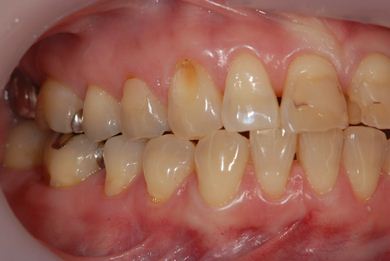

治療前

• 治療前